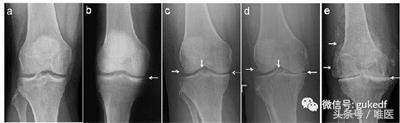

经常会遇到有人发现自己“关节疼、肿”,到医院拍片,诊断为“滑膜炎”(图1a,1b)、“骨质增生”(图1c,1d,1e),还有诊断为“关节炎”的(图1d,1e)。那到底是哪种病?我们对这几种病名分别了解一下。

图1.膝关节的各种X线拍片表现

从上可见,关节软骨磨损、骨关节炎就会继发滑膜炎。因为在常规X线片上无法观察到明显的关节周围骨质增生(骨赘、骨刺形成),或关节间隙变窄(图1c,1d,1e),因此被称之为“滑膜炎”。

患者关节肿痛,拍片子后看到报告单上描述的“骨质增生”,同时观察到X线片上关节(股骨或胫骨)周缘或髁间棘处增生的骨质(图1c,1d,1e左侧和中间白箭头),就断定自己得了“骨质增生”(有了“骨刺”)。

从前面我们可以知道,过度活动或年龄增大会造成关节磨损。轻度的关节损伤会造成“滑膜炎”;重度的关节损伤或年龄增大造成关节磨损会导致“退行性骨关节炎”,也就是常说的“关节炎”(图1c,1d,1e)。